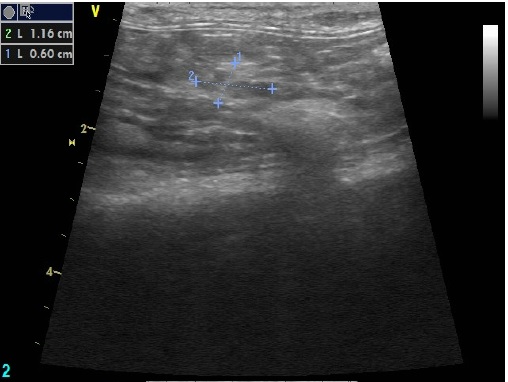

El siguiente paso en nuestro protocolo fue realizar una ecografía abdominal con la que finalmente confirmamos nuestras sospechas: Yodi tenía quistes en ambos ovarios, lo que le producía un desequilibrio hormonal importante. La solución, por lo tanto, fue pasar por quirófano: esterilizándola sus problemas deberían solucionarse.